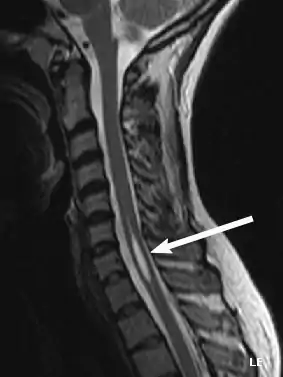

Diagnosis

Physicians now use magnetic resonance imaging (MRI) to diagnose syringomyelia. The MRI radiographer takes images of body anatomy, such as the brain and spinal cord, in vivid detail. This test will show the syrinx in the spine or any other conditions, such as the presence of a tumor. MRI is safe, painless, and informative and has greatly improved the diagnosis of syringomyelia.[14][15][16][17][18][19][20][21][22][23][24][25]